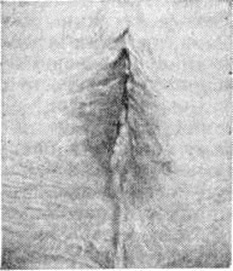

При осмотре кожа наружных половых органов истончена, сморщена; большие половые губы плоские, лишены волос; малые половые губы и клитор сглажены или отсутствуют, вход во влагалище сужен (рис.).

Рис

Изменения вульвы при краурозе: половые губы сглажены и лишены волос, коша сморщена и истончена.